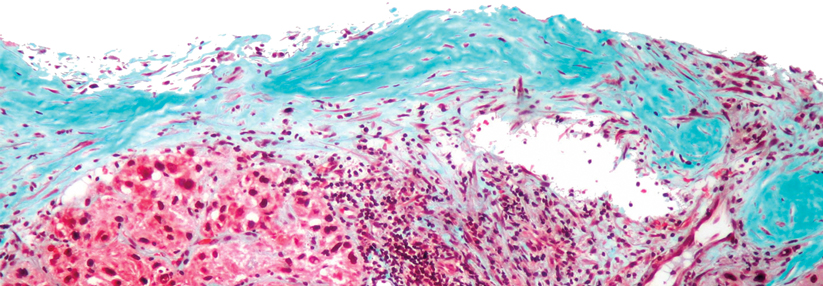

Schwerer Alpha-1-Antitrypsin-Mangel erhöht das Krebsrisiko. Schwerer Alpha-1-Antitrypsin-Mangel erhöht das Krebsrisiko. © iStock/Md Saiful Islam Khan

Betroffene mit schwerem Alpha-1-Antitrypsin-Mangel scheinen ein erhöhtes Risiko für Krebserkrankungen zu haben. Das gilt sowohl für Tumoren der Leber als auch für nicht-hepatische Tumoren.